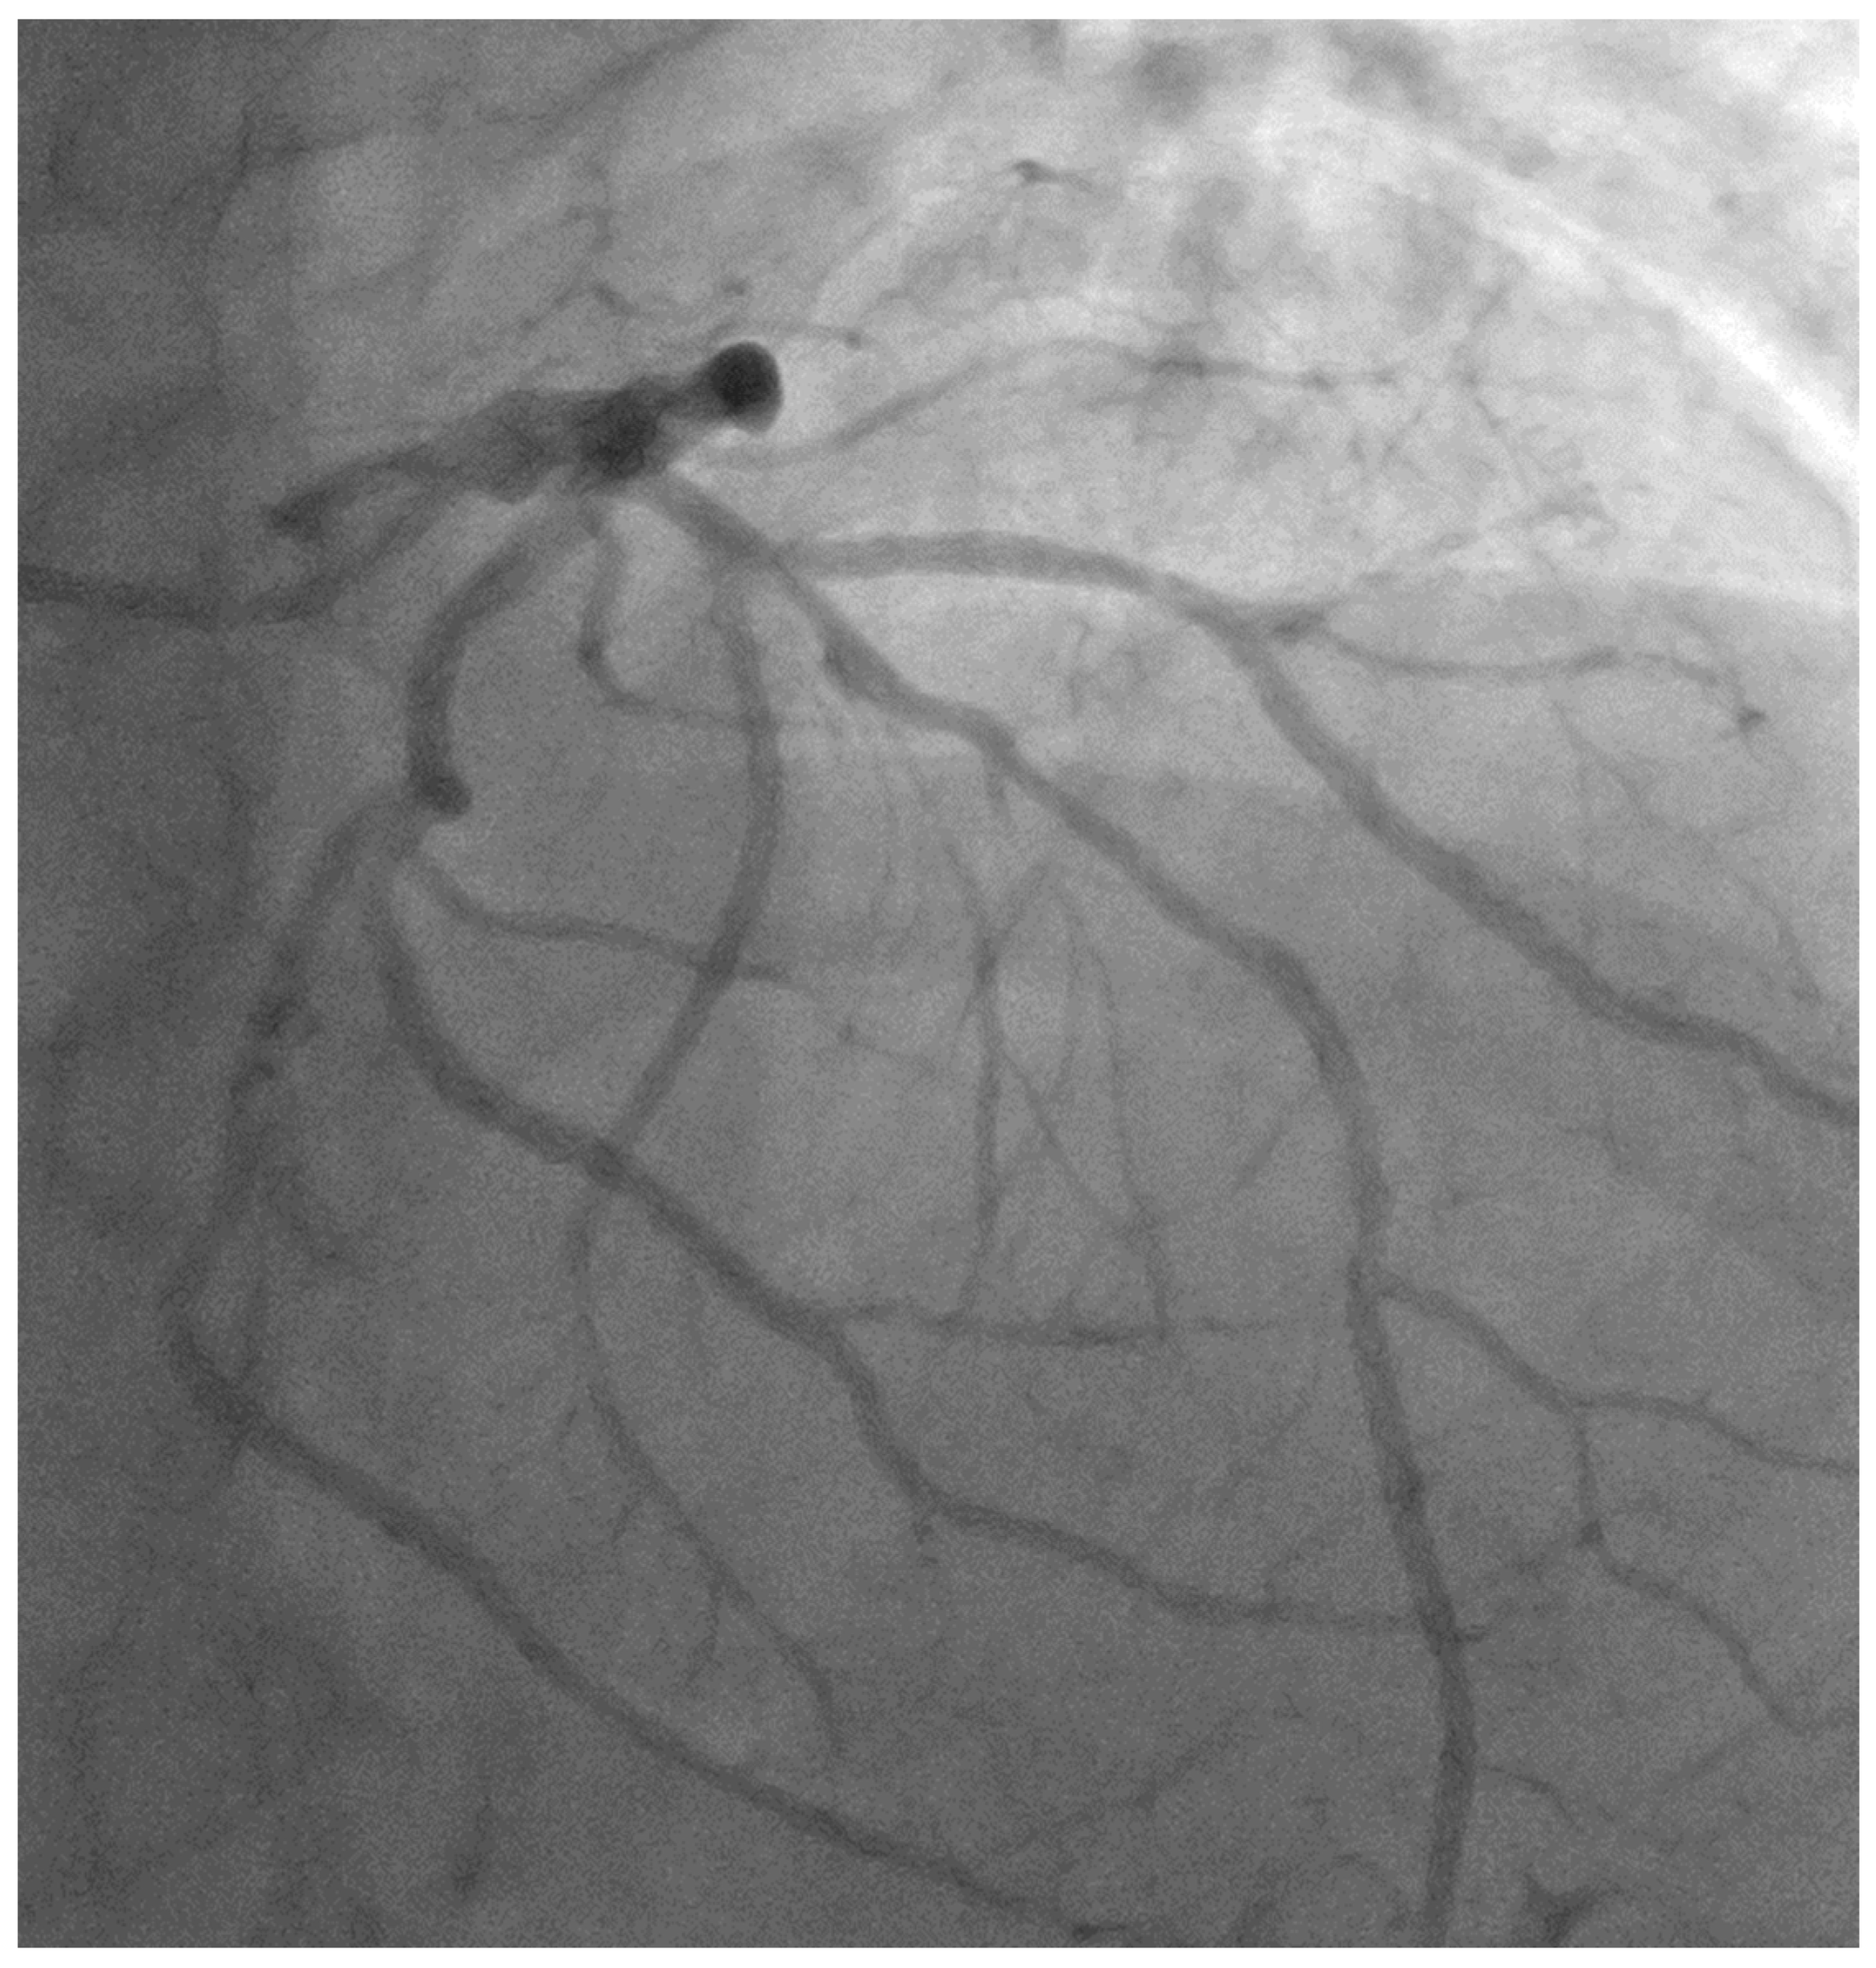

- Case # 1

| Case 1 | 56 yo | LAD/D1 | LAD stent, D1 balloon | 4 years | 4 y, SR |

| Case 1 | LAD ISR | D1 is an 80% lesion |